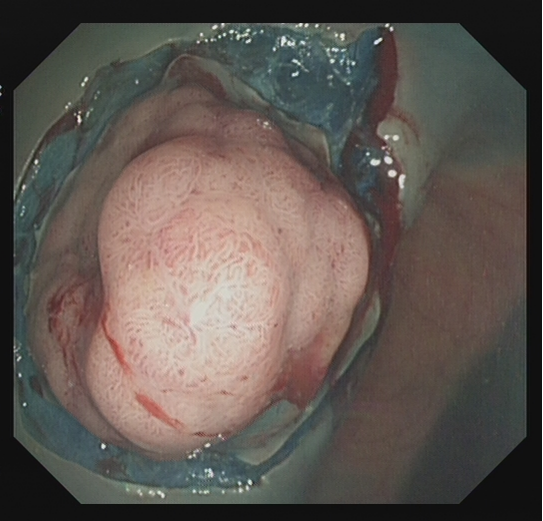

对于直径大于2 cm且需一次性切除病变、抬举征阴性的腺瘤及部分早癌、EMR 残留或复发治疗困难者,可以实行 ESD 治疗,一般步骤为:

1.内镜染色后明确病灶边界,环周标记(病灶边界较为清晰者也可不标记),